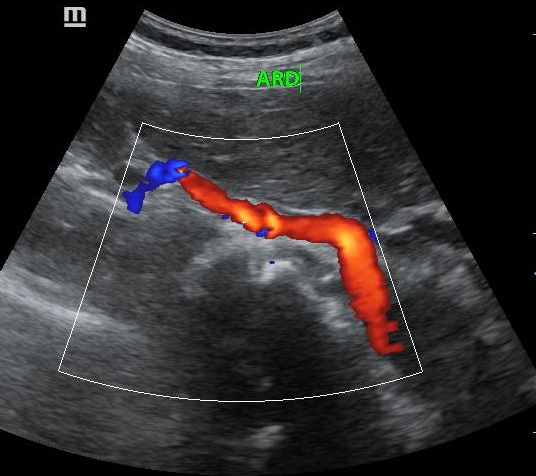

ECODOPPLER

El Eco Doppler es un tipo de ultrasonido que estudia el flujo de sangre que se transporta por las arterias y venas; es decir, permite conocer la cantidad, velocidad y consistencia del flujo sanguíneo en un momento concreto.

• Doppler Abdominal

• Doppler Arterias renales